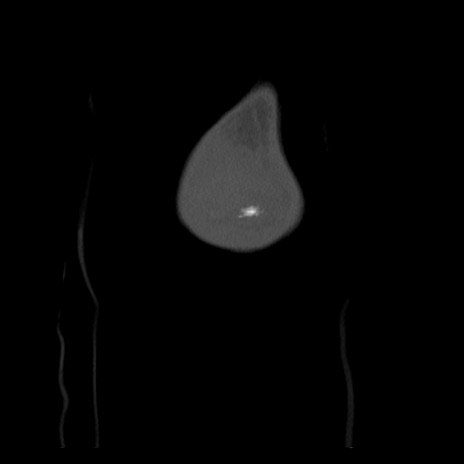

右膝関節CT

横断像